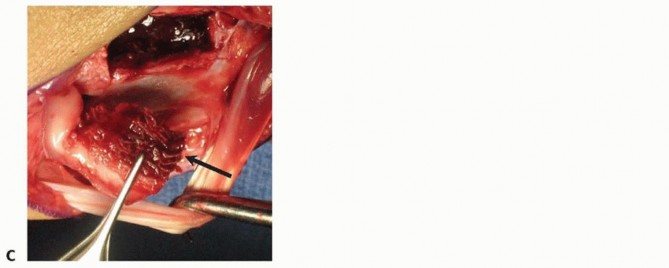

Preparation of the Scaphoid Nonunion Site

Once the pedicle is identified and safely isolated, attention is turned to the scaphoid nonunion. The capsule of the radiocarpal joint is incised longitudinally, usually in line with the interval between the third and fourth dorsal compartments, to expose the dorsal aspect of the scaphoid. The nonunion site is typically obscured by dense, hypertrophic fibrous tissue and sclerotic bone edges. Using a combination of fine rongeurs, sharp curettes, and a high-speed motorized burr (used with copious cool saline irrigation to prevent thermal necrosis), the fibrous nonunion is meticulously debrided.

The debridement must be aggressive and uncompromising. The surgeon must excavate all necrotic, sclerotic, and fibrous tissue until healthy, punctate bleeding bone is encountered in both the proximal and distal fragments—the so-called "paprika sign." If the proximal pole is truly avascular, it may not bleed vigorously, but the sclerotic margins must still be resected to expose the underlying trabecular network, allowing the incoming vascularized graft to integrate. During this debridement, the surgeon must be careful to preserve the volar cortical hinge of the scaphoid, if intact, to maintain anatomical length and prevent destabilization of the construct. Once the defect is fully prepared, its dimensions are carefully measured using a sterile caliper to guide the subsequent graft harvest.